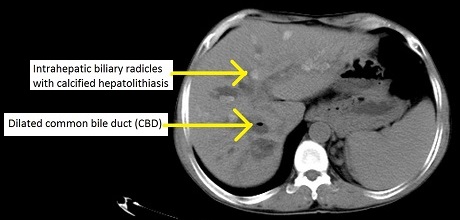

Primary Sclerosing Cholangitis

Primary sclerosing cholangitis (PSC) is inflammation and fibrosis of intrahepatic and extrahepatic bile ducts.

Primary sclerosing cholangitis (PSC) has a periductal fibrosis with an onion-skin appearance.

On contrast imaging, uninvolved areas expand, giving them a beaded look.